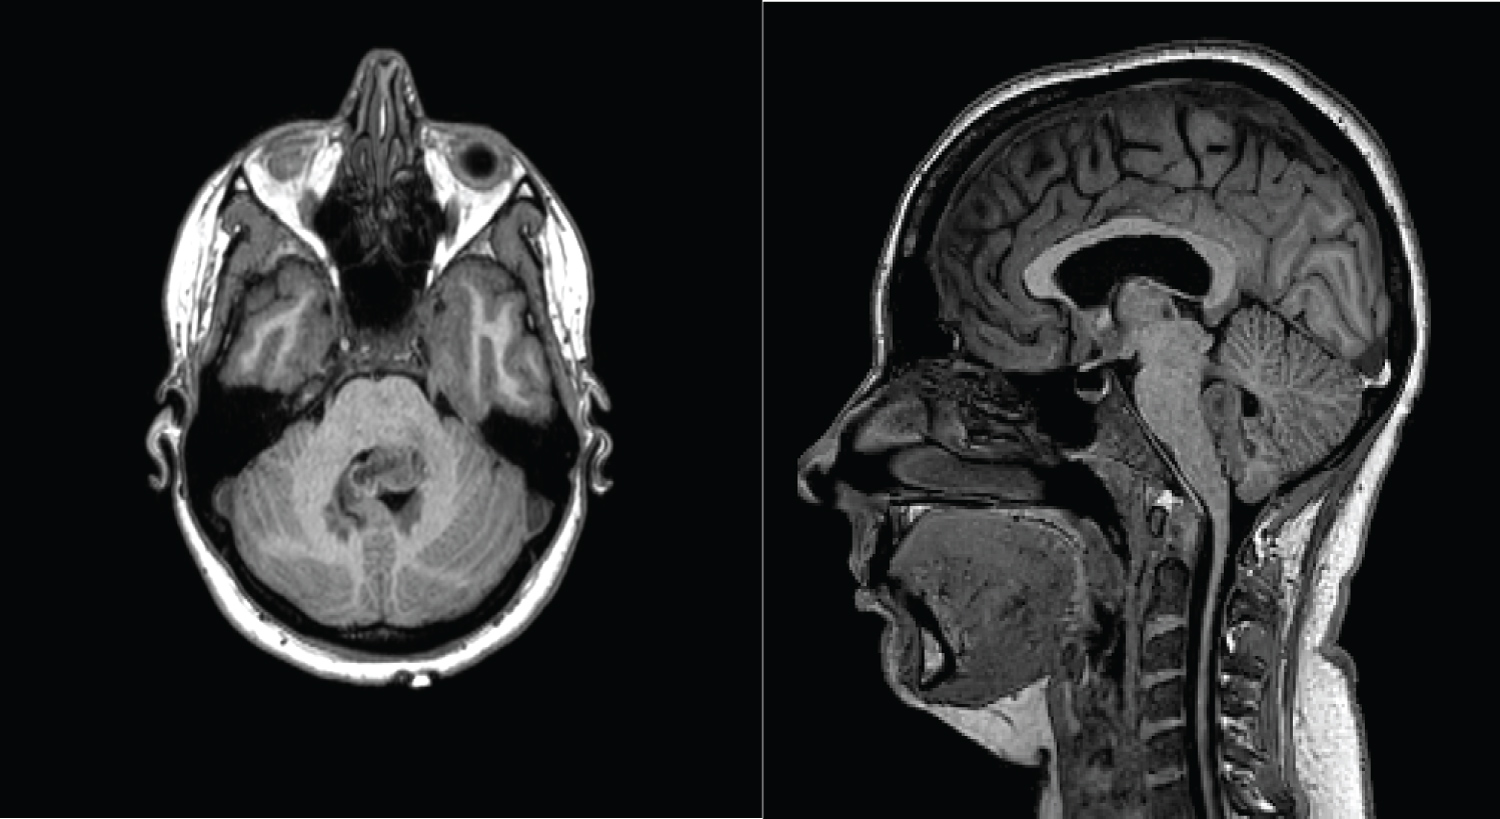

On arrival to our unit, we performed MRI sequences which include T2 weighted, susceptibility weighted, and T1 volume pre-and post-contrast and 3-D time-of-flight MRA. These showed a serpiginous lesion within the fourth ventricle that exhibited a flow void on T2-weighted imaging and appears to arise from terminal left posterior inferior cerebellar artery (Figure 2 and Figure 3).

Figure 2: MRI T1- pre-contrast axial and sagittal showing the mixed intensity 4th Ventricular tumour. View Figure 2

Figure 3: Post-contrast and FLAIR sequences demonstrate the 4th ventricular lesion with flow void. View Figure 3

Our patient's imaging demonstrated a lesion filling the entire fourth ventricle with a flow void on T2 weighted imaging. There was increased signal on 3-D time of flight angiography. The presence of a flow void in the T2 weighted imaging was a unique feature that allowed us to suspect an aneurysm in imaging that would have otherwise been diagnosed as a tumour.